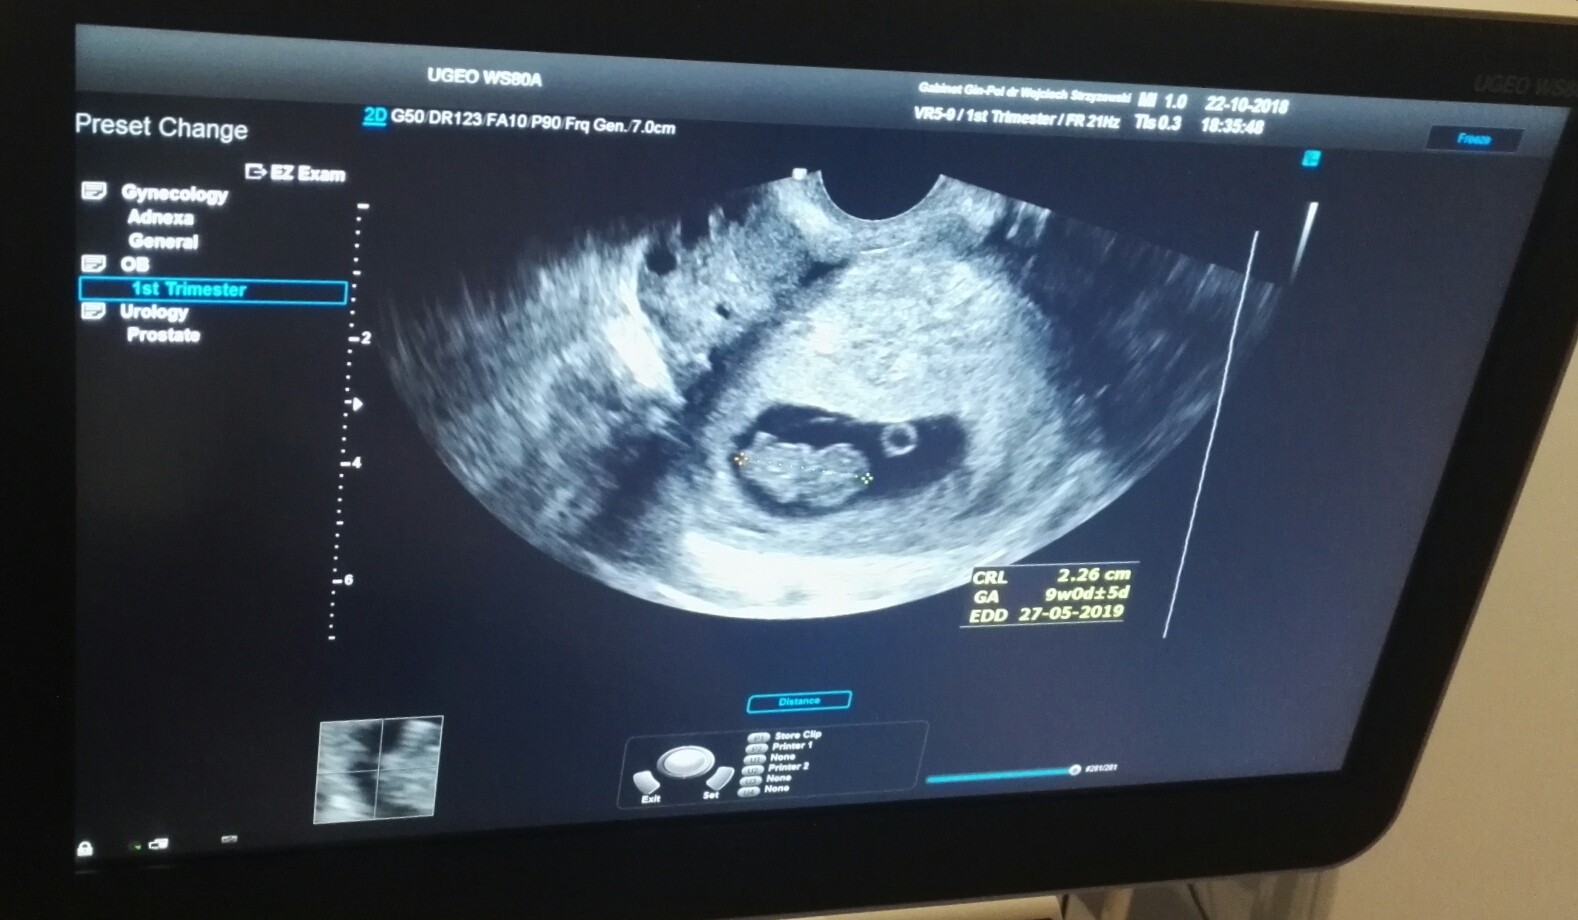

No dokładnie [emoji39]No tak tak teraz sa roznice a pozniej dzieci rodza sie wtedy kiedy im pasuje a nie kiedy jest termin ;-)